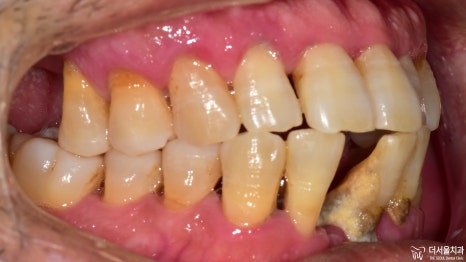

1) 정면

다량의 치석과 치은 퇴축,

치주염과 치간이개가 관찰되고 있습니다.

하악 우측 중절치는 아예 상실되어 있었습니다.

2) 측면

이쪽도 정면과 마찬가지였습니다.

구강 내에 전체적으로 번진 치주 질환 때문에

잇몸 및 치아의 상태가 좋지 않습니다.